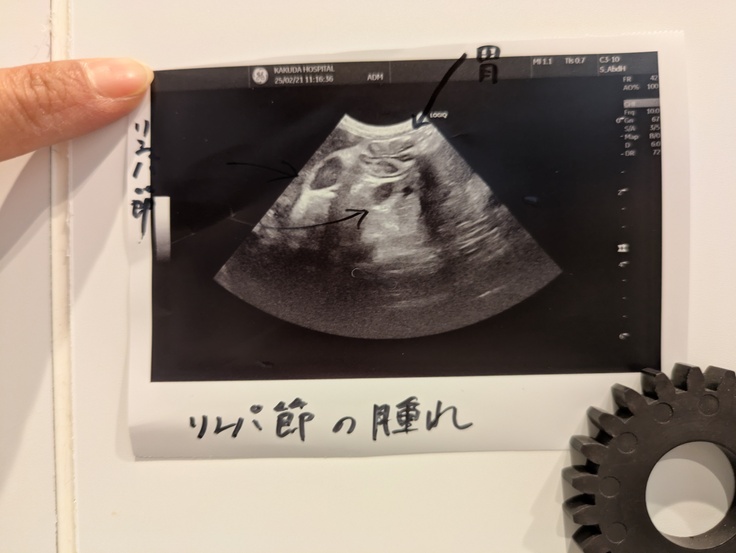

そして[もなか君]

[もなか君]も嘔吐が続いたことで受診。

私は喉や腸になにかがあるんじゃないかと疑っていましたがエコーの結果リンパ節が腫れていることが分かりました。

飲み薬は吐いてしまうので抗生剤の注射となりました。

また、血液検査では炎症は口腔内にあることが分かりやはり抜歯とかスケーリングだね。というお話になりました。

また吐き気が気になっていましたので吐き気止めと点滴をしていただきました。